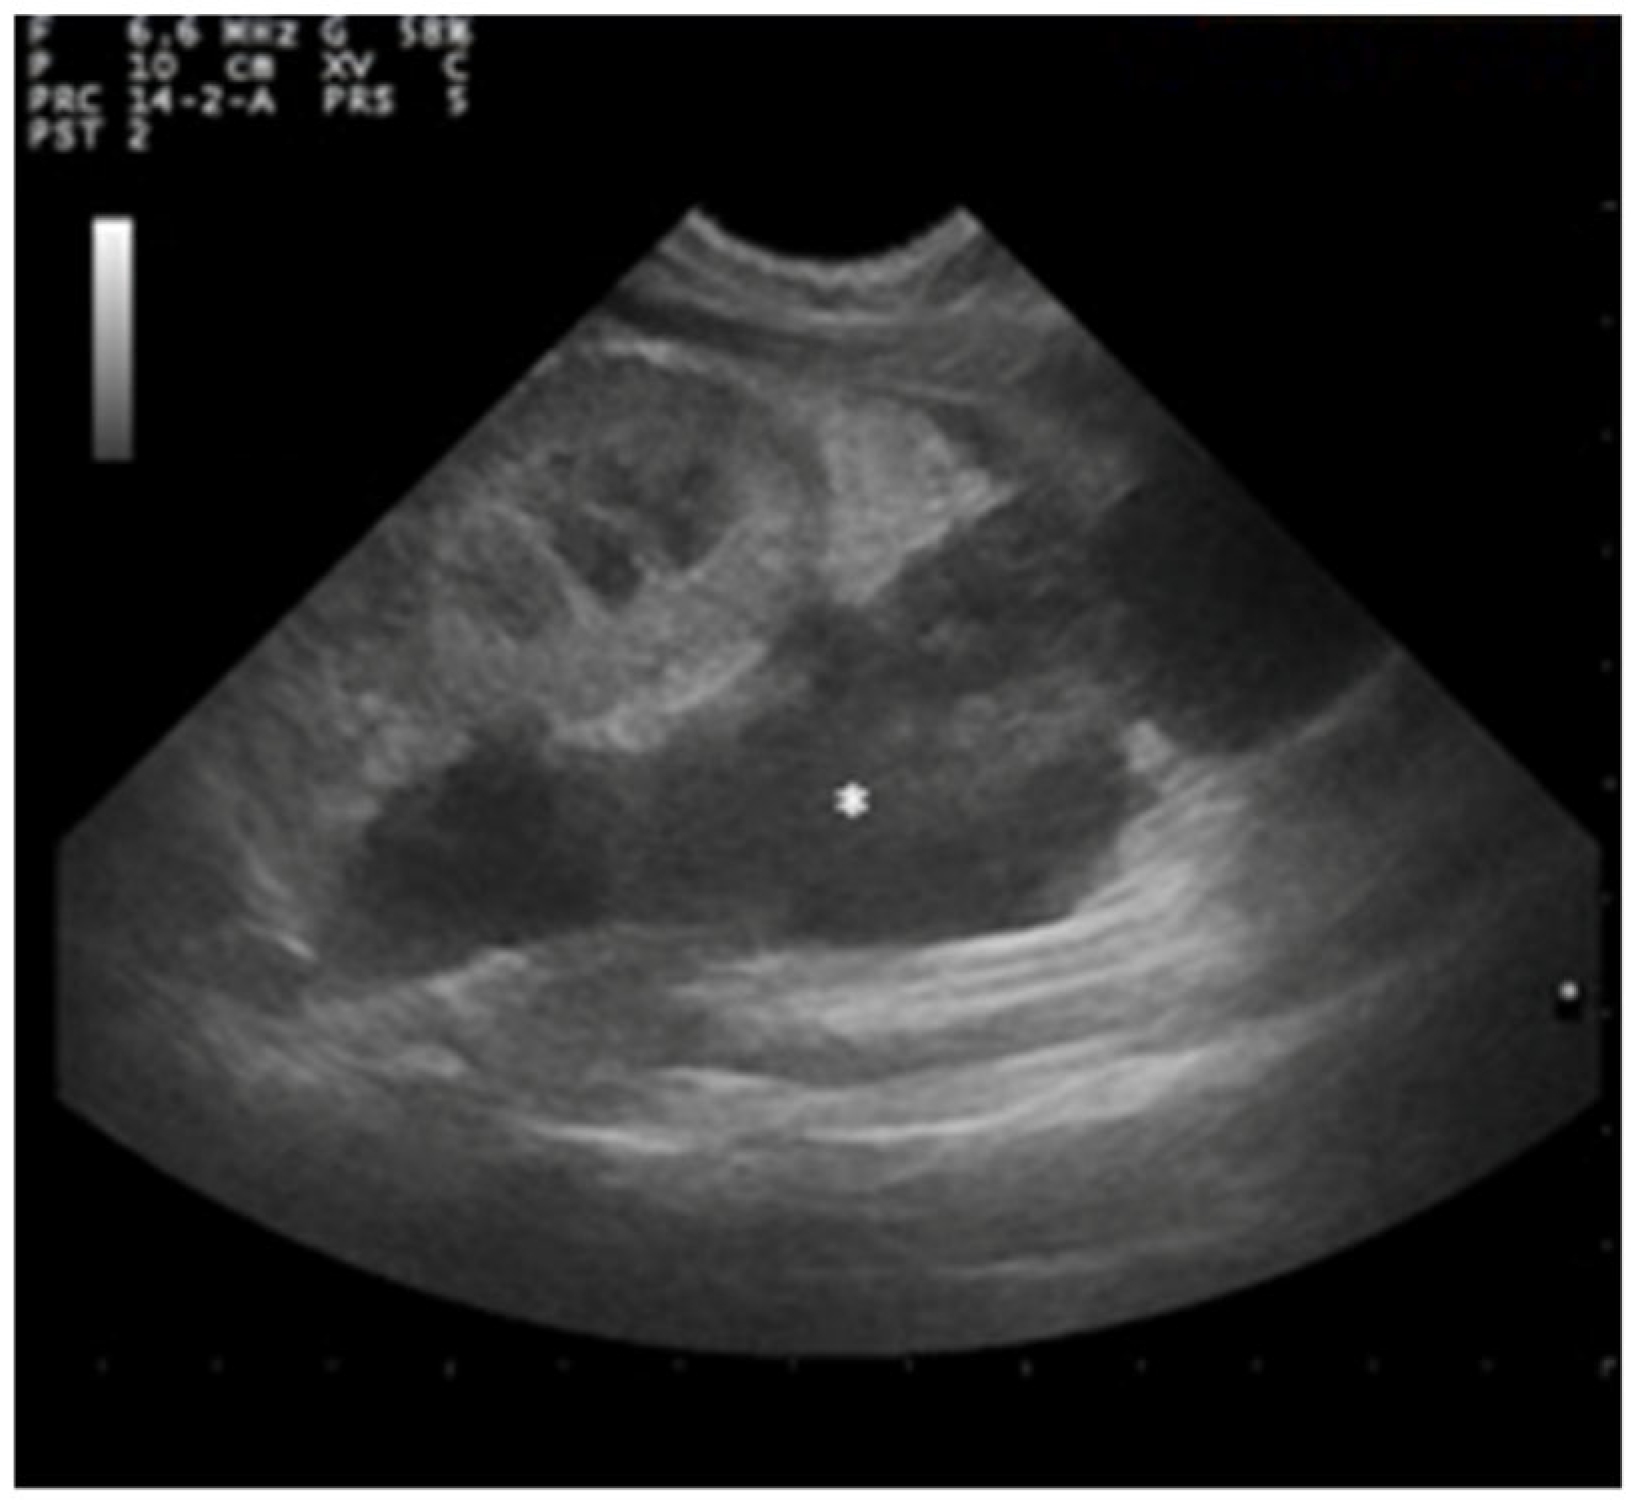

A large perirenal collection of anechoic fluid containing small areas of echogenic tissue attributable to intraperitoneal fat was observed in the left hemiabdomen. A capsule surrounding the lesion showed an inhomogeneous pattern with no evident stratigraphy (Figure 4).

Figure 4.

Ultrasound examination of left kidney showing anechogenic area in the left hemiabdomen (asterisk) containing small areas of echogenic tissue attributable to intraperitoneal fat.